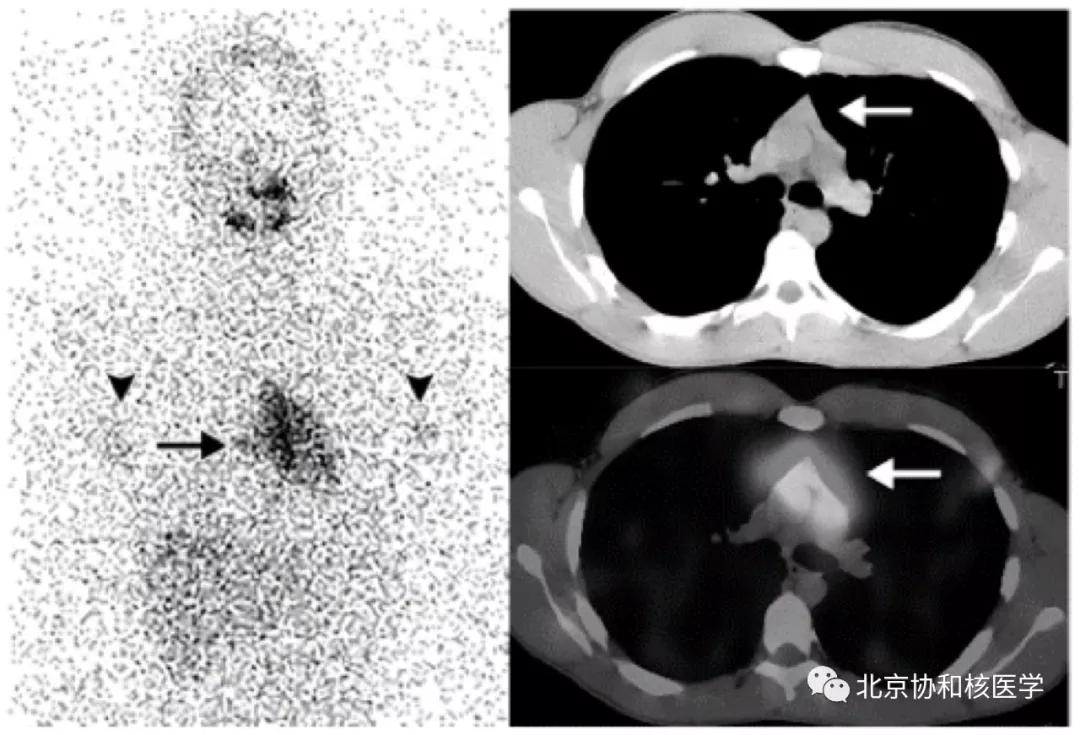

肺鳞癌所致碘摄取(后位图像),同时可见颈部甲状腺残余病灶: